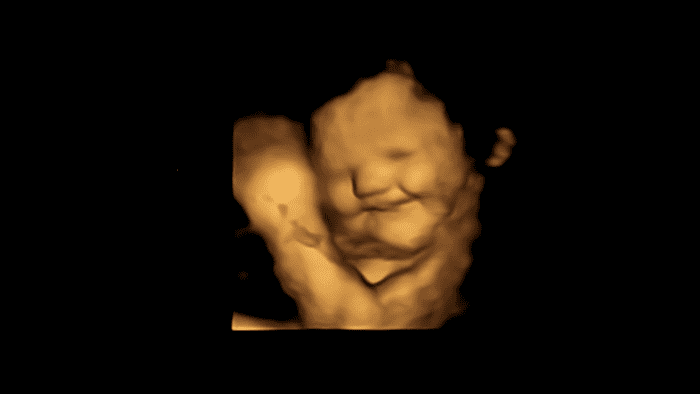

أظهرت الأجنة "وجهاً مبتسماً" عند تعرضها إلى الجزر، بينما أظهرت "وجهاً باكياً" عند الاستجابة إلى الكالي.

الأجنة تضحك للجزر وتبكي من الكالي.

استجابة "الوجه الضاحك" عند الجنين لدى تناول الأم الجزر. حقوق الصورة: جامعة دورهام/ جامعة أستون.